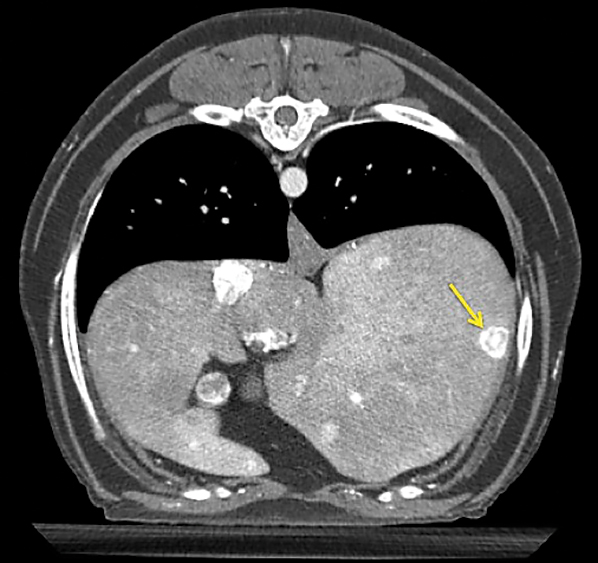

A thoracoabdominal dual-phase CT scan was performed with the goals of further evaluating the pancreatic nodule, ruling out obvious metastatic disease, and planning for possible surgery. The CT scan revealed a 1.8 × 2.6-cm nodule in the body of the pancreas that demonstrated marked neovascularization in the early arterial phase and mild peripheral contrast enhancement relative to the remainder of the pancreas in the main arterial and portal phase scans (Figure 2). A strong contrast-enhancing liver nodule was noted in the arterial phase of the CT angiogram (Figure 3). Other hepatic nodules noted on ultrasound were not visualized in the arterial or mixed portal/venous angiographic phases. No evidence of nodular pulmonary metastasis was evident.